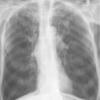

COPD

Date: 06/06/2004

Views: 14534